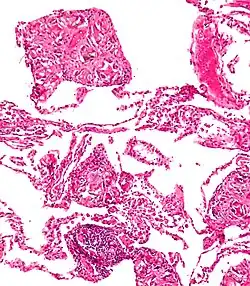

A coin seen on AP CXR in the esophagus